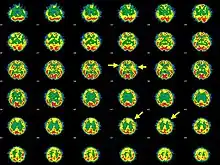

Brain SPECT transaxial images of a patient afflicted with Hashimoto's encephalopathy.